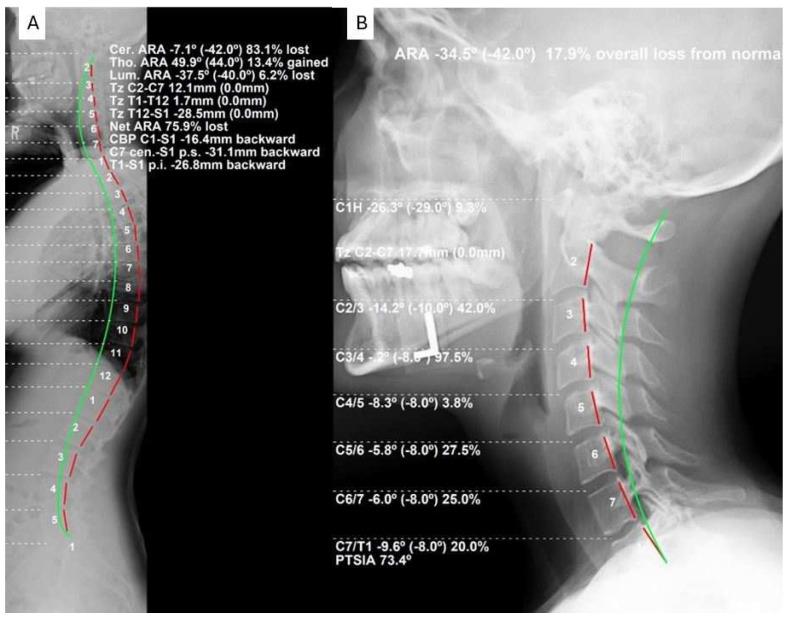

This study assessed the relationship between cervical spine parameters taken on standing full-spine lateral radiographic images compared to sectional lateral cervical radiographs. Full-spine (FS) and sectional lateral cervical (LC) radiographs from four spine treatment facilities across the USA retrospectively provided data collected on 220 persons to assess the comparison of three sagittal cervical radiographic measurements between the two views. The measures included cervical lordosis using the absolute rotation angle from C2-C7, sagittal cervical translation of C2-C7, and atlas plane angle to horizontal. Linear correlation and R models were used for statistical comparison of the measures for the two views. The mean values of the three measurements were statistically different from each other: C2-C7 translation (FS = 19.84 ± 11.98 vs. LC = 21.18 ± 11.8), C2-C7 lordosis (FS = -15.3 ± 14.63 vs. LC = -18.32 ± 13.16), and atlas plane (FS = -19.99 ± 8.88 vs. LC = -22.56 ± 8.93), where all values were < 0.001. Weak-to-moderate-to-strong correlations existed between the full-spine and sectional lateral cervical radiographic variables. The R values varied based on the measurement were R = 0.768 ( < 0.001) for sagittal cervical translation of C2-C7 (strong), R = 0.613 ( < 0.001) for the absolute rotation angle C2-C7 (moderate), and R = 0.406 ( < 0.001) for the atlas plane line (weak). Though a linear correlation was identified, there were consistent intra-person differences between the measurements on the full spine versus sectional lateral cervical radiographic views, where the full-spine view consistently underestimated the magnitude of the variables. Key sagittal cervical radiographic measurements on the full spine versus sectional lateral cervical radiographic views show striking intra-person differences. The findings of this study confirm that full spine versus sectional lateral cervical radiographic views provide different biomechanical magnitudes of cervical sagittal alignment, and caution should be exercised by health care providers as these are not interchangeable. We recommend the LC view for measurement of cervical sagittal alignment variables.

本研究评估了站立位全脊柱侧位X线片与颈椎节段侧位X线片上颈椎参数之间的关系。回顾性地从美国四个脊柱治疗机构收集了220人的全脊柱(FS)和颈椎节段侧位(LC)X线片数据,以评估两种视图下三个颈椎矢状位X线测量值的比较。测量指标包括使用C2-C7的绝对旋转角度测量颈椎前凸、C2-C7的矢状位平移以及寰椎平面与水平面的夹角。采用线性相关性和R模型对两种视图下的测量指标进行统计学比较。这三项测量的平均值在统计学上彼此不同:C2-C7平移(FS = 19.84±11.98,而LC = 21.18±11.8)、C2-C7前凸(FS = -15.3±14.63,而LC = -18.32±13.16)和寰椎平面(FS = -19.99±8.88,而LC = -22.56±8.93),所有这些值均<0.001。全脊柱与颈椎节段侧位X线变量之间存在弱到中到强的相关性。根据测量指标不同,R值有所变化:C2-C7矢状位平移的R = 0.768(<0.001,强相关),C2-C7绝对旋转角度的R = 0.613(<0.001,中度相关),寰椎平面线的R = 0.406(<0.001,弱相关)。虽然确定了线性相关性,但全脊柱视图与颈椎节段侧位X线视图的测量值之间存在一致的个体内差异,全脊柱视图始终低估了变量的大小。全脊柱视图与颈椎节段侧位X线视图上关键的颈椎矢状位测量值显示出显著的个体内差异。本研究结果证实,全脊柱视图与颈椎节段侧位X线视图提供了不同的颈椎矢状位排列生物力学大小,医疗保健提供者应谨慎使用,因为它们不可互换。我们建议使用LC视图来测量颈椎矢状位排列变量。